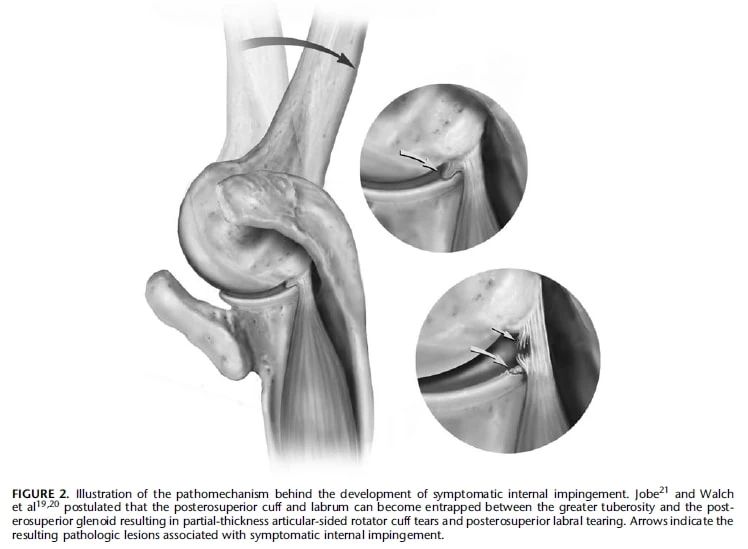

어깨 내부 충돌은 어깨의 회전근개와 관절낭의 연부 조직이 견갑골(견갑골의 일부)과 상완골(위팔뼈) 사이에 끼이거나 눌려서 발생하는 일련의 증상을 설명하는 용어입니다. 이는 일반적으로 어깨가 납치(몸에서 멀어짐)되거나 외부로 회전(바깥쪽으로 돌림)되는 등 특정 위치에 있을 때 발생합니다. 팔목과 부르사가 수정체낭 아치 구조에 끼이는 외부 충돌과는 다릅니다. 내부 충돌의 정확한 원인은 아직 논란이 되고 있지만 특정 어깨 자세에서 정상적으로 발생하는 것으로 보입니다. 내부 충돌의 영상 소견으로는 부분적 두께의 팔목 인대 파열, 음순 병리, 뼈 변화 등이 있을 수 있습니다.

내부 충돌 증후군은 후상부 충돌과 전상부(전방) 충돌의 두 가지 유형이 있습니다. 후상부 내부 충돌은 상부 및 극상근 힘줄의 접합부에 가까운 후상부 회전근 개가 후상부 글렌노이드와 접촉할 때 발생합니다. 반면에 전상위 충돌은 전회전근개와 전상위 관절와 사이의 충돌을 포함합니다. 이러한 질환은 회전근개와 관절낭의 연부 조직이 관절와순 또는 관절와순과 상완골 사이에 충돌하는 것이 특징입니다.